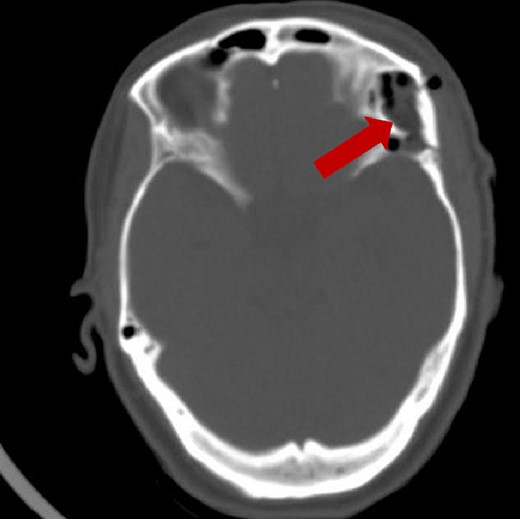

A post-operative brain CT scan demonstrated total resection of the lesion (Fig. 4). The postoperative course was uneventful, and the patient was discharged without any neurological deficits.

Post-operative brain axial CT scan illustrating the total resection of the lesion.